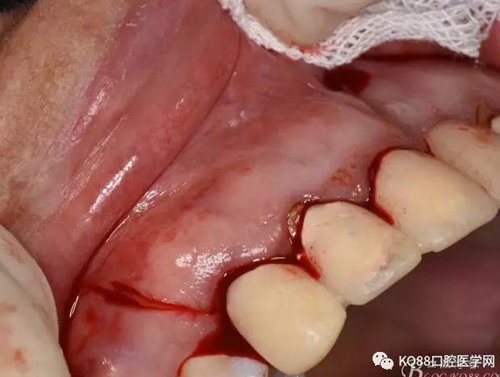

圖4.腭側(cè)觀:12根尖正對的腭粘膜隆起、有波動感

圖5.唇側(cè)局部浸潤麻醉

圖6.腭側(cè)浸潤麻醉